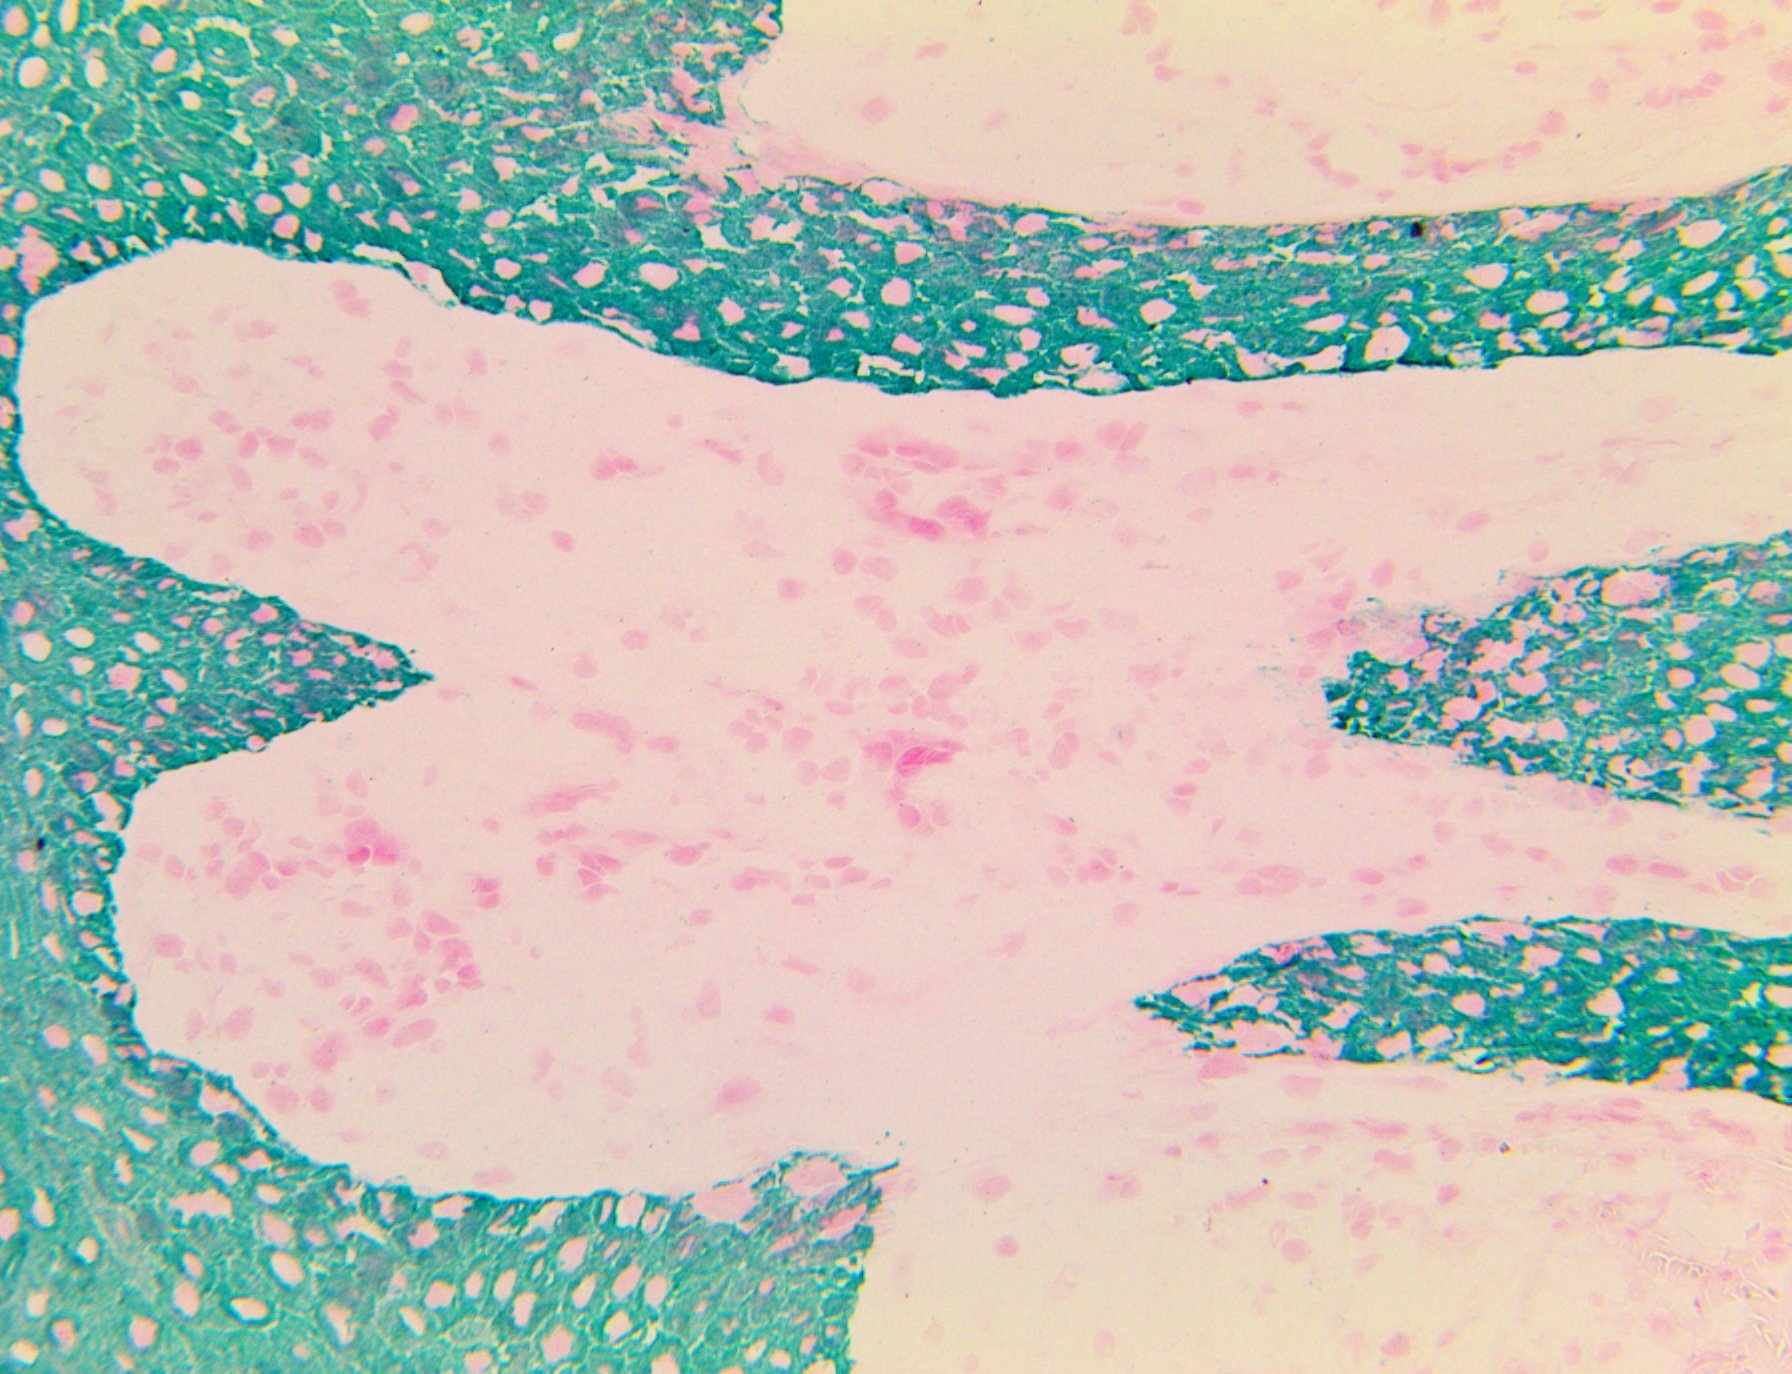

| Intended Use For Mohs In Vitro Diagnostic Use Summary and Explanation Cytokeratin MNF116 is a broad-spectrum anti-cytokeratin reacting with intermediate and low-molecular-weight keratins, ranging from 40 through 58 kD, corresponding to cytokeratin 5, 6, 8, 17 and 19. It shows a broad pattern of reactivity with human epithelial tissues from simple glandular epithelial to stratified squamous epithelia, like epidermis, mammary gland ducts, and tracheal epithelium. Cytokeratin MNF116 is a useful aid for the classification of neoplasms of epithelial origin including Squamous Cell Carcinoma, Small Cell Carcinoma, Sarcomatoid Carcinoma, Spindle Cell Carcinoma, Epithelioid and Spindle Cell component of Malignant Mesothelioma and Adenocarcinoma. A wide range of soft tissue tumors are also positive with cytokeratin MNF116: monophasic and biphasic Synovial Sarcoma, vascular neoplasms including Epithelioid Hemangioendothelioma, Epithelioid Angiosarcoma, Epithelioid Sarcoma. Desmoplastic Small Round Cell Tumors require cytokeratin positivity for diagnosis. Smooth muscle tumors and Plasmacytoma may demonstrate aberrant expression of cytokeratin MNF116. Antibody Type Mouse Monoclonal Clone MNF116 Isotype IgG1 Reactivity Paraffin, Frozen Localization Cytoplasmic Control SCC, BCC Presentation Anti – Cytokeratin MNF116 is a mouse monoclonal antibody derived from cell culture supernatant that is concentrated, dialyzed, filter sterilized and diluted in buffer pH 7.5, containing BSA and sodium azide as a preservative. Mohs IHC Procedure Specimen Preparation of Mohs Frozen Tissues Embed the specimen in OCT inside a cryostat. Cut sections at 4-5 µm and mount on a positively charged glass slide such as the Bio SB Hydrophilic Plus Slides (BSB 7028) or in the lower third of the TintoDetector Cap Gap slides (BSB 7006). Air dry the slide at room temperature for 2 minutes and then incubate the slide at 60 °C for 3 minutes in an incubator or dry bath. Fix in 100% acetone or 10% NBF for 2 minutes at room temperature. Using NBF 10% produces better morphology. Rinse with distilled water and air dry the slides for another 2 minutes at room temperature. IHC Detection Procedure Transfer slides to ImmunoDNA washer, TBST or PBST buffer. For manual staining, perform antibody incubation at ambient temperature. For automated staining methods, perform antibody incubation according to instrument manufacturer’s instructions. Wash slides with ImmunoDNA washer, TBST, PBST or DI water. Continue IHC detection protocol. Wash slides between each step with ImmunoDNA washer, Tris or PBS Buffer solution. Abbreviated Mohs Immunohistochemical Protocol Do HIER with Citrate in Pressure Cooker (100 – 121 °C ) for 1 min. Cool off Wash with Buffer (TBST or PBST) Do PIER, proteolytic Digestion, with Mohs ImmunoDigestor for 30 sec. Wash with Buffer (TBST or PBST) Incubate slides with Peroxidase Blocker for 30 seconds Wash with Buffer (TBST or PBST) Incubate CK MNF116 for 4 min Wash with Buffer (TBST or PBST) Incubate with HRP Label for 3 min. Wash with Buffer (TBST or PBST) PrepareDAB Brown (1 drop of DAB chromogen in 1 ml of DAB Buffer; mix well) or HRP Green (1 drop of HRP Green chromogen in 1 ml of HRP Green Buffer, mix well) Incubate with DAB or HRP Green for 2 min Wash with Buffer (TBST or PBST) Counterstain with Hematoxylin or Nuclear Fast Red for 30 seconds Wash with Buffer (TBST or PBST) Mount with AquaMounter or PermaMounter For best results with the IHC of CK MNF116, we recommend using Mohs Frozen sections fixed NBF 10% for 2 min., then HIER with Citrate at 100 – 110 °C for 2 min., plus PIER with Mohs ImmunoDigestor (BSB 0324 – 0326 )at room temperature for 30 sec. This protocol can also be used with FFPE Tissues retrieved with Citrate or EDTA. |